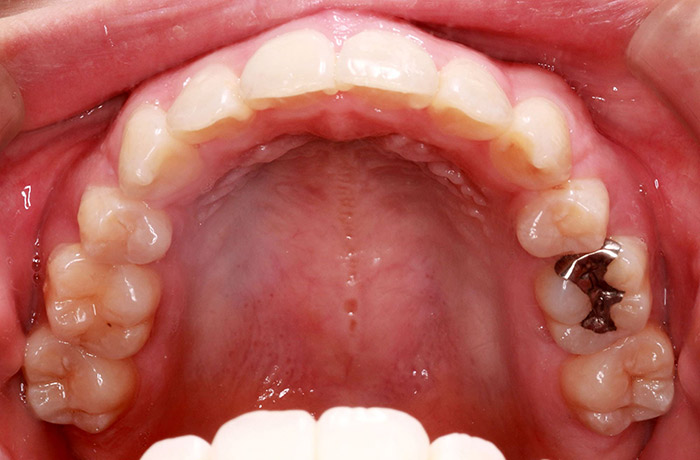

K様

治療前

before

年齢 27歳

性別 女性

治療名称 マウスピース型カスタムメイド矯正歯科装置(インビザライン)・コンプリヘンシブパッケージ(フルパッケージ)

総額治療費用 770,000円(税込10%) 金額備考 精密検査料・診断料 33,000円(税込10%)

治療期間 1年11か月 通院頻度など 40日ごと

1枚につき10日装着を指示しました。

患者の症状 上顎前歯の前突、八重歯

治療方法 上下左右の第一小臼歯抜歯で、マウスピース型カスタムメイド矯正歯科装置による矯正

治療結果 上顎前歯の前突、八重歯が改善されました。

歯並びをより良くするために追加でアライナーを発注しました。

リスク/副作用 決められた時間装着する必要があります。